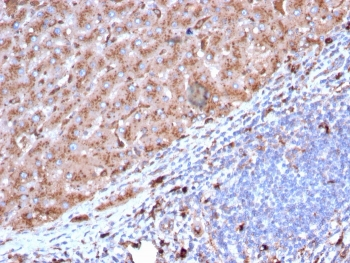

Cathepsin D Antibody

| Description | Cathepsin D Antibody |

| Tested applications | FC, ICC, IHC, IP, WB |

| Reactivity | Human, Mouse |